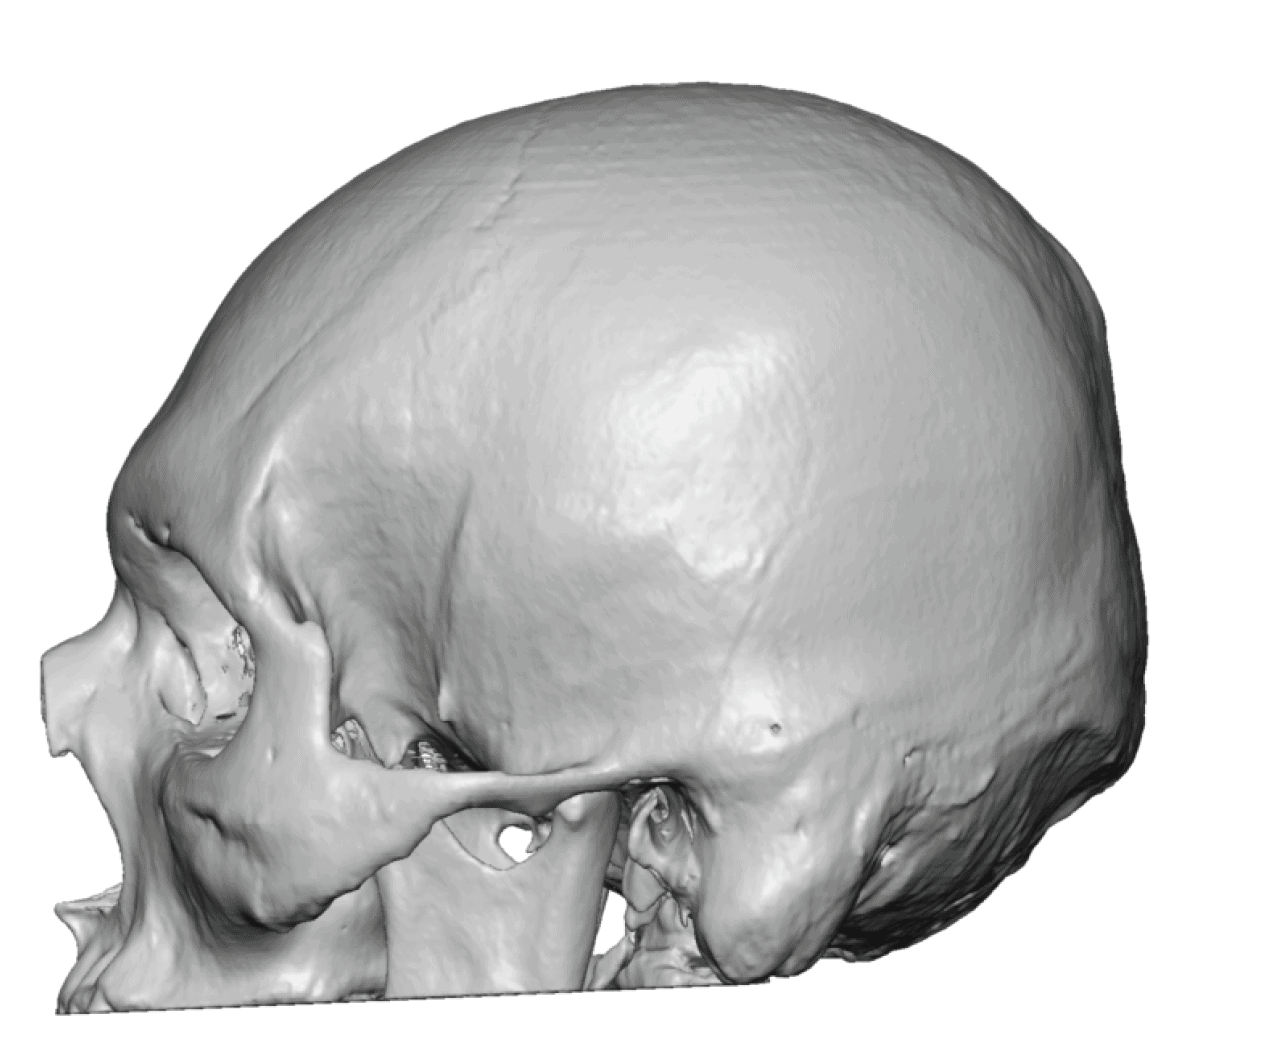

Patient 28

Desire for rounder shape to the top of the head from a congenital parasagittal deficiency skull shape.

Custom skull implant designed to fill in the parasagittal deficiencies.

Desire for rounder shape to the top of the head from a congenital parasagittal deficiency skull shape.

Custom skull implant designed to fill in the parasagittal deficiencies.